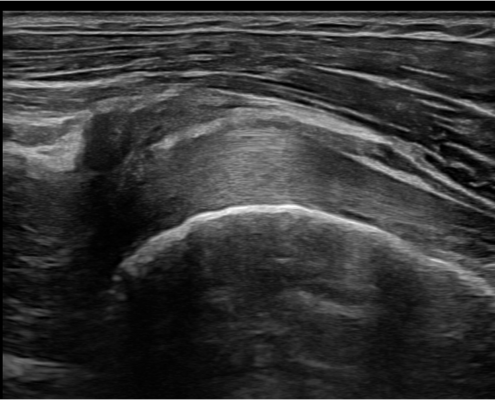

Bij ziekteprocessen zoals reuma kan de gehele schouder betrokken raken, ook de bicepspees. Soms alleen de bicepspeesschede. Dit komt minder vaak voor dan gedacht. Het is goed te beoordelen met echografie.

We kijken zelden alleen naar de bicepspees. Sterker nog, de biceps is het startpunt van het lichamelijk en echografisch onderzoek waarbij we naar alle structuren van de schouder kijken.

Bicepspees injectie

De bicepspees kan een langdurige aanjager van de pijn zijn. Als rust en fysiotherapie niet meer werken, kan een injectie geplaatst worden met corticosteroïden. Indien dit vlak bij de bicepspees geplaatst moet worden, is een echogeleide injectie een goede keuze. Hierbij wordt door middel van echografie gekeken waar de naald zich bevindt en wordt direct bij de pees of achter in het gewricht corticosteroïden ingebracht.